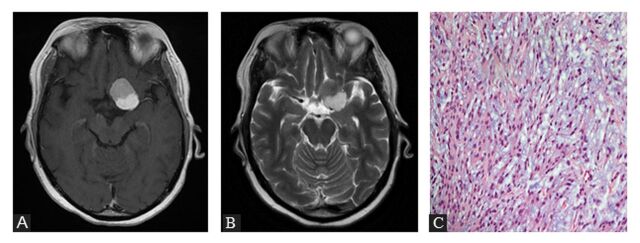

Abstract Image